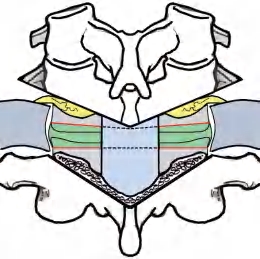

(2)暴露:切开皮肤及皮下组织,用自动撑开器撑开切口防止出血,保留棘上韧带和棘突的末端(图2-48),因为C 6 以上为双尾棘突,C 6 以下的棘突末端呈鼓槌状,利用这一特点将Luque棒夹在棘突的两侧不易滑脱,固定效果满意。沿棘突的两侧纵向切开,剥离暴露双侧椎板,将自动撑开器插入切口的深部,撑开两侧的椎旁肌肉,暴露椎板和横突(图2-49)。

图2-48 沿棘突切口,保留棘上韧带和棘突末端,以备做Luque棒夹持棘突固定法

(5)内固定:手术者将两根Luque棒预折成所需要的弯度,事先应在棘突间棘间韧带上打孔,穿过双股1.0mm直径的Luque钢丝,将双侧的Luque棒夹持固定在棘突上,利用其棘突末端的膨大部,挡住双侧夹持棘突的Luque棒,使其不易滑脱,其固定效果十分可靠(图2-54)。

图2-54 Luque棒加钢丝夹持棘突固定法,因为强直性脊柱炎患者的棘突间韧带已骨化强直,给夹持棘突内固定创造了优越的条件